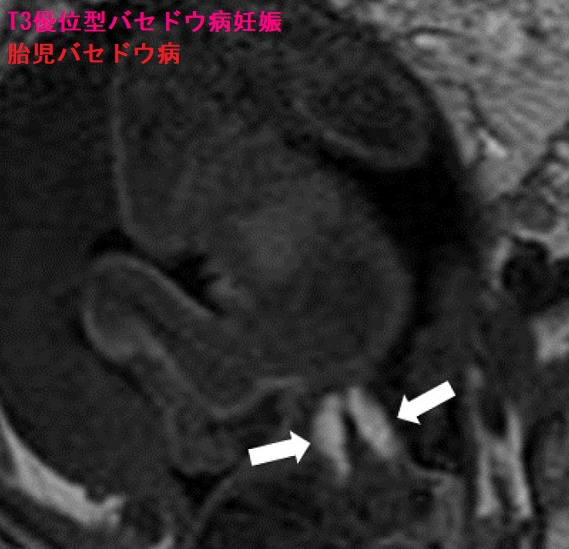

T3優位型バセドウ病妊娠

T3優位型バセドウ病妊娠ではFT4ではなくFT3に基づいて抗甲状腺薬の投与量を調整しなければなりません。母体のFT4値に基づいて調整したため、母体のバセドウ病は悪化し、胎児甲状腺機能亢進症/バセドウ病が現れた報告があります。[Kobe J Med Sci. 2021 Feb 8;66(4):E153-E158.]